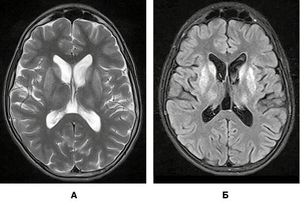

вгоруОсновними ознаками гепатоцеребральної дегенерації, які дозволяє виявити дослідження головного мозку за методом магнітно-резонансної томографії (МРТ), є зміни в базальних ядрах та стовбурі. Головні з них — це підвищення МР-сигналу за режимів Т2 та Т2/Flair від головок хвостатих ядер, блідих куль, лушпин та таламусів (рис. 1).

У режимі Т2 візуалізується підвищення МР-сигналу від покришки середнього мозку, на тлі якого спостерігаються чіткі контури червоних ядер і чорної субстанції, створюючи характерний вигляд «голови панди» (ознака «великої панди», рис. 2А). У тому ж режимі на межі середнього мозку та моста, на рівні верхніх мозочкових ніжок візуалізується підвищення сигналу від дорзальних відділів середнього мозку, що створює характерний вигляд «голови малої панди» (ознака «малої панди», рис. 2Б).